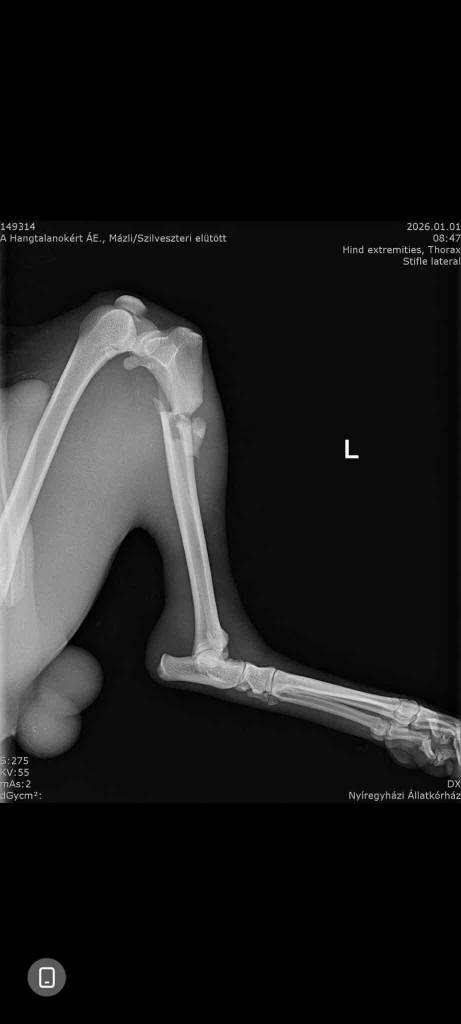

. Mázli hatte in der Tat Glück, dass er gefunden wurde und Hilfe bekam. Glück, dass es bei einem Schienbeinbruch blieb! Der junge Rüde wurde am 31.12 von einer Mitarbeiterin des Tierheims auf der Straße gefunden und durfte die Nacht bei ihr Zuhause im Warmen verbringen. Am Donnerstag kam er in die Tierklinik, wo der besagte Schienbeinbruch diagnostiziert wurde. Zum Glück hat er keine inneren Blutungen. Gechipt ist er allerdings auch nicht. Naheliegend ist, dass Mázli mit einem Auto kollidiert ist.